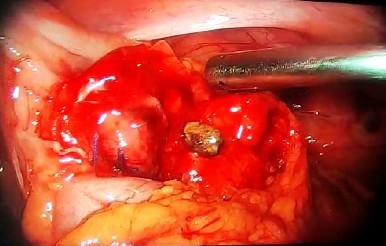

On October 20 (day 4), the patient was reoperated: a diagnostic laparoscopy evidenced approximately 280 cc seropurulent drainage at the pouch of Douglas, right paracolic gutter and right subphrenic space; multiple adhesions in the right lower quadrant; cecal appendix with undamaged stump and one coprolite inside, which was removed (Figure 2).

Figure 2 Dropped appendicolith removed from the appendiceal stump. Appendiceal stump ligation with one knot of polyglycolic acid suture (left side of the image).

On November 23 (day 8), the patient was reoperated and the following was observed: intestinal obstruction due to adhesions of the ileum, proximal to the right paracolic gutter, with scarce purulent drainage, although the fecalith was not located at that level. Therefore, a systemic examination of the entire small intestine was performed, evidencing an appendicolith of 1 cm in diameter located at the mesentery of the jejunum, at 1 m from the angle of Treitz, with erosion of the mesentery caused by the appendicolith (Figure 4).

Figure 4 Dropped appendicolith at the mesentery. Erosion of the mesentery caused by the appendicolith (left side of the image).